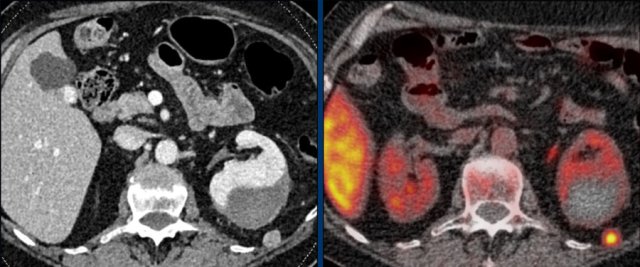

Axial venous phase CT in mediastinal and bone window setting Axial venous phase CT in mediastinal and bone window setting

Images depict mediastinal and bone window setting of a patient with a bulky heterogeneously enhancing right adrenal tumor.

This was proven to be an adrenocortical carcinoma.

There is a faint, ill-defined liver lesion in segment 6 and there are non-specific sclerotic changes in the body of T12.

Continue with the PET-image...

PET-CT performed for complete staging shows intense uptake in the adrenal tumor, indicative of its malignant nature.

There is also intense uptake in two liver metastases and in a bone metastasis in T12.

Approximately 20-40% of patients with an adrenocortical carcinoma present with metastases at diagnosis.